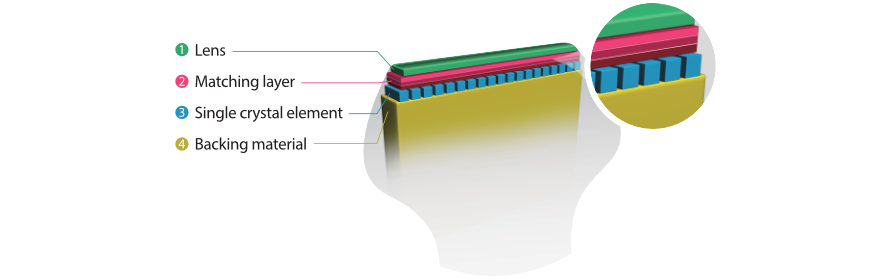

Tecnologia trasduttore 3T con cristallo singolo

Fornendo immagini pi├╣ nitide, tutte le sonde compatibili con M9 sono dotate della tecnologia Mindray tecnologia trasduttore 3T, unica nel suo genere. Migliorato con l'aggiunta della tecnologia monocristallo, M9 offre una migliore penetrazione e un flusso dinamico del colore, in particolare durante la scansione di pazienti difficili.